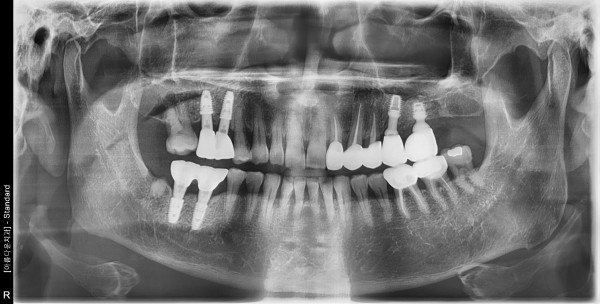

67세 남자 상하악 뼈 이식후 임플란트 식립